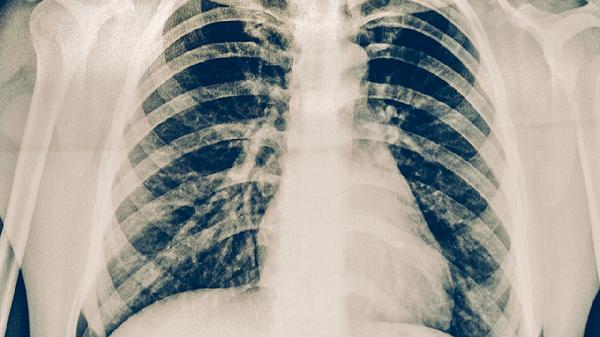

治疗间质性肺炎的药物主要有糖皮质激素、免疫抑制剂、抗纤维化药物、抗氧化剂和抗炎药物。